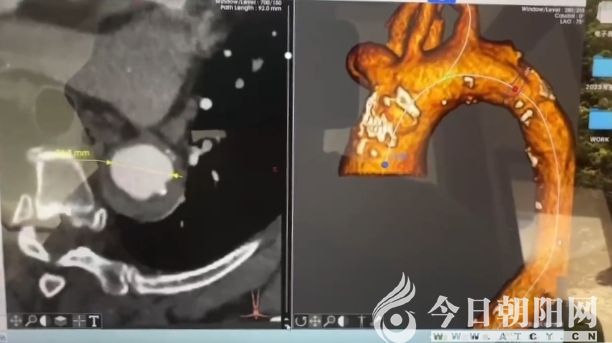

主動(dòng)脈夾層壁間血腫CASTOR支架植入手術(shù)視頻截圖

考慮到若將患者送往上級(jí)醫(yī)院診治,轉(zhuǎn)運(yùn)途中存在一定風(fēng)險(xiǎn),心血管內(nèi)三科主任王彥隆向家屬認(rèn)真講解了病情特性,并積極安撫患者及家屬的焦慮情緒,最終患者及家屬?zèng)Q定在北票市中心醫(yī)院進(jìn)行介入治療。在北京積水潭醫(yī)院賈偉教授指導(dǎo)、北票市中心醫(yī)院導(dǎo)管室全力支持下,王彥隆帶領(lǐng)主治醫(yī)師王浩然、住院醫(yī)師韓哲開展手術(shù),經(jīng)過1小時(shí)30分的默契合作,成功為患者植入了CASTOR支架,挽救了患者寶貴的生命。